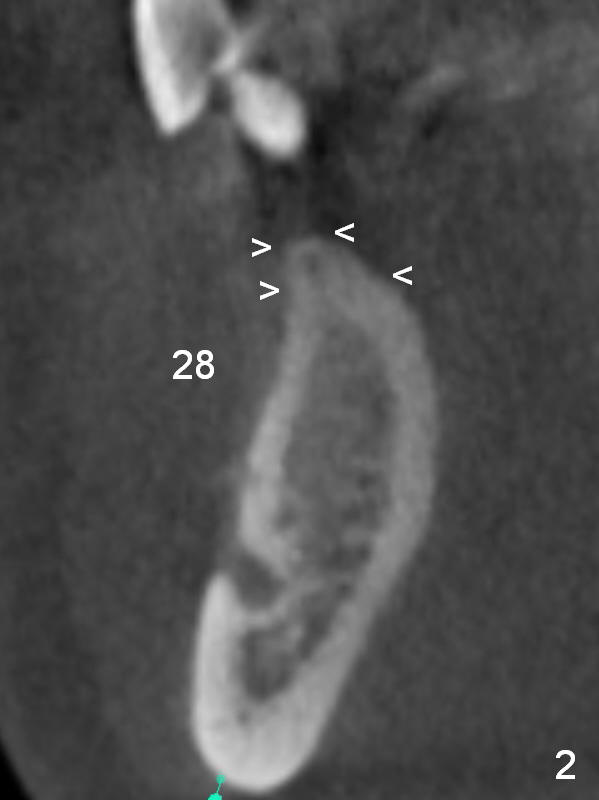

A 39-year-old man had an accident, which caused loss of several teeth 20 years ago. The patient (wearing removable partial dentures) decides to restore #28,29 with implants first (Fig.1 CBCT sagittal section). Coronal section at #28 shows narrow ridge coronally (Fig.2). To place an implant, the pointed ridge top has to be removed about 4.5 mm (Fig.3). Probably due to severe bone resorption post extraction, an angled abutment may be needed as much as 20 degree (Fig.4).